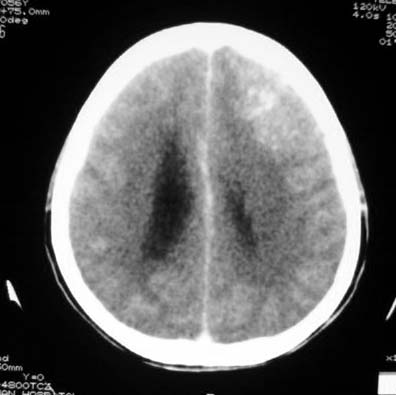

标题: CT7268:左额顶部病变增强片. [打印本页]

标题: CT7268:左额顶部病变增强片.

左侧额顶叶有条带状钙化的不规则形占位,增强呈不均匀轻度强化,局部颅骨受侵蚀变薄,典型的少支胶质细胞瘤。

比较典型的少枝胶质细胞瘤ct表现,局部额骨垂直板有侵蚀变薄